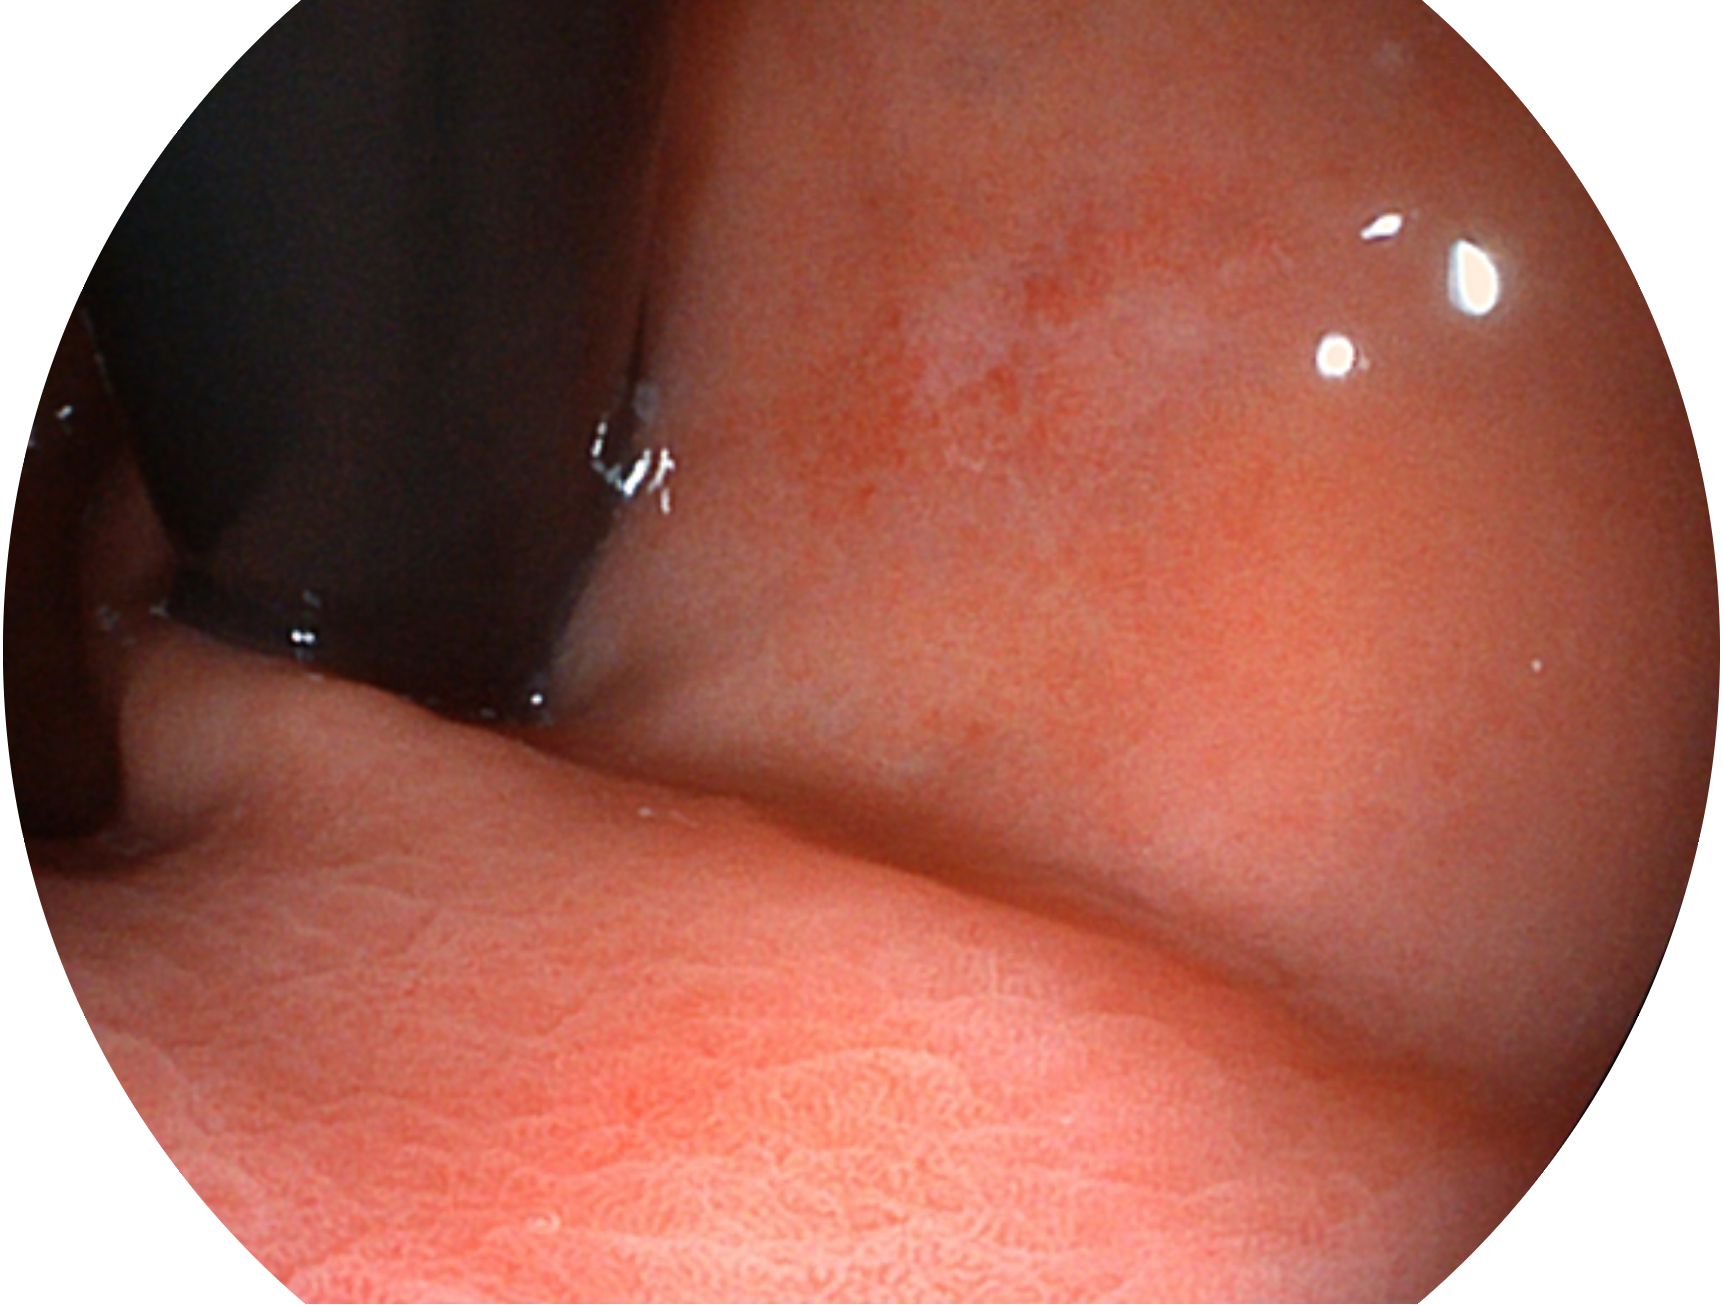

• 白光图像 VIST图像